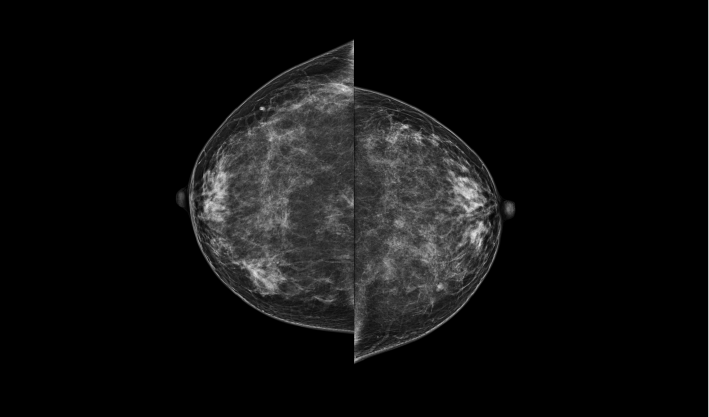

頭尾位(CC位) 內外斜位(MLO位) 補充體位(根據需求)

一鍵式視圖切換